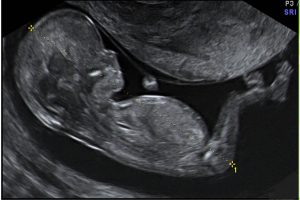

Diplomados en Ultrasonografía